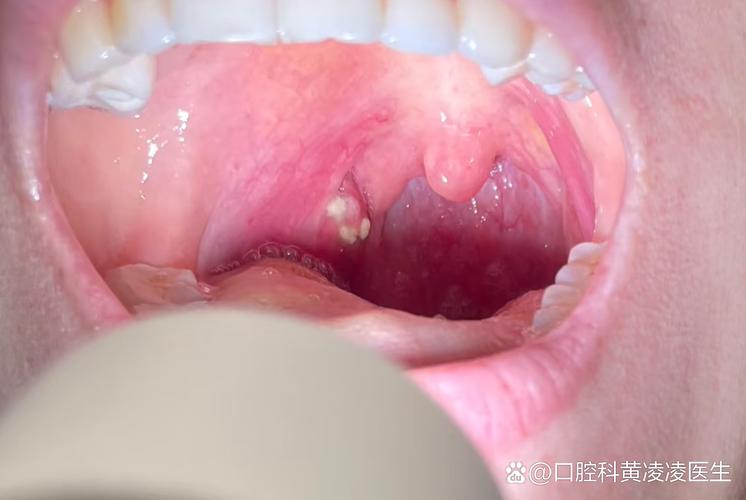

口腔疱疹性咽峡炎图片长啥样? 口腔疱疹性咽峡炎的典型特征描述 疱疹性咽峡炎是一种由肠道病毒(最常见的是柯萨奇病毒A型)引起的急性传染病,主要影响儿童,但成人也可能感染,它的“病灶”主要集中在口腔后部,也就是咽峡部。 主要症状(全身性) 发热:通常是首发症状,体温可高达39-40℃,可持续2-4天。 咽喉剧痛:这是最突出的症状,孩...